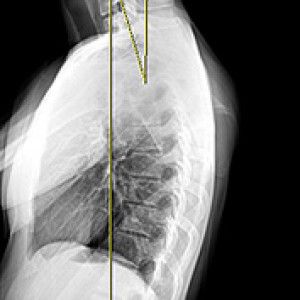

턱관절 + 경추 + 척추 + 골반을 함께 교정

몸은 도미노처럼 연쇄적으로 틀어지기 때문에 한 부위만 교정하는 것으로는 문제가 해결되지 않습니다. 대부분의 거북목과 굽은등은 턱관절 불균형, 어깨비대칭, 골반틀어짐, 척추휘어짐을 동반하기 때문에 함께 교정하는 것이 좋습니다.

Before & After

해당 사진은 수정없는 실제 치료사진입니다.

환자의 치료결과는 환자의 상태, 치료방법 등에 따라 차이가 발생할 수 있습니다.